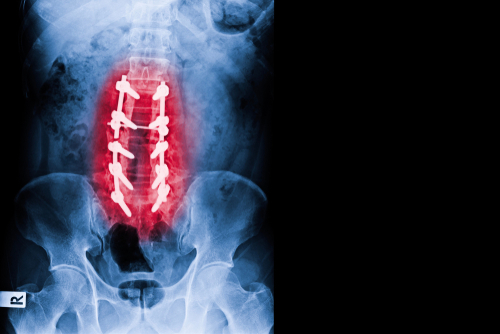

When sciatica is causing severe pain, it is time to see your doctor. Doctors can perform a physical exam and order a series of tests to rule out any serious spinal or nervous system problems. Some tests will include x-rays, CT scans, or MRI tests.

X-rays will show any bone spurs or narrowing of spinal arteries; however, MRI and CT scans will reveal more information about the cause of your sciatica pain. Once doctors determine what is causing the pain in your back, they can prescribe treatment to reduce or eliminate the symptoms.

If there is a severe structural problem, it may be necessary to remove the protruding disc from the spinal canal to treat the herniated disc properly.

Injuries to the spine can occur from several different causes such as falls, disease, sports injuries, car accidents, and more.